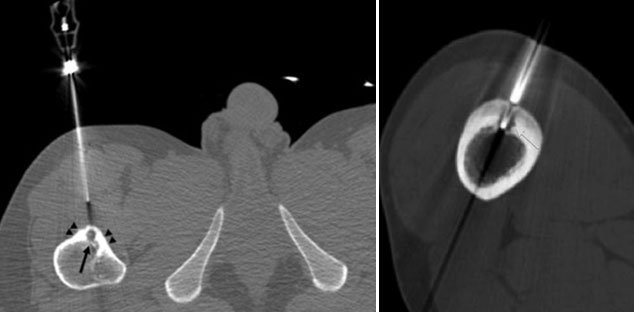

Procedure in which the lesion is burnt by producing heat. A special needle is placed within lesion and radiofrequency ablation waves are applied for particular time and temperature. This procedure is done under general anesthesia and CT Scan guidance.